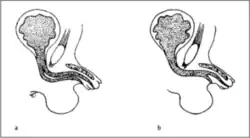

Den Abbildungen liegt folgende Typisierung zugrunde:[2]

- Typ 1 blind endende überzählige Urethra

- (a) epispade Lokalisation der akzessorischen Urethra

- (b) die akzessorische mündet an normaler Stelle (loco typico), die funktionelle Urethra hypospad

- Typ 2 komplette Duplikatur, beide Harnröhren verlaufen innerhalb des Penisschaftes

- (a) von normaler Länge

- (b) von kurzer Länge

- Typ 3 komplette Duplikation mit funktioneller Urethra und außerhalb des Penisschaftes mündender Harnröhre

- Typ 4 Duplikatur mit partieller oder kompletter kaudaler Duplikation mit zweiter Harnblase und eigener Ableitung (epispad)